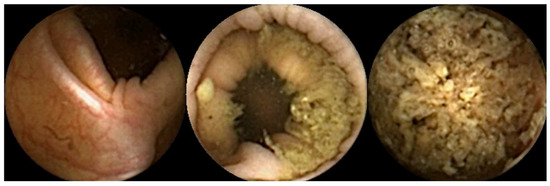

- Buijs, M.M.; Ramezani, M.H.; Herp, J.; Kroijer, R.; Kobaek-Larsen, M.; Baatrup, G.; Nadimi, E.S. Assessment of bowel cleansing quality in colon capsule endoscopy using machine learning: A pilot study. Endosc. Int. Open 2018, 6, E1044–E1050. [Google Scholar] [CrossRef]

- Leighton, J.A.; Rex, D.K. A grading scale to evaluate colon cleansing for the PillCam COLON capsule: A reliability study. Endoscopy 2011, 43, 123–127. [Google Scholar] [CrossRef] [PubMed]

- de Sousa Magalhães, R.; Arieira, C.; Boal Carvalho, P.; Rosa, B.; Moreira, M.J.; Cotter, J. Colon Capsule CLEansing Assessment and Report (CC-CLEAR): A new approach for evaluation of the quality of bowel preparation in capsule colonoscopy. Gastrointest. Endosc. 2021, 93, 212–223. [Google Scholar] [CrossRef] [PubMed]

- Mascarenhas Saraiva, M.J.; Afonso, J.; Ribeiro, T.; Cardoso, P.; Mendes, F.; Martins, M.; Andrade, A.P.; Cardoso, H.; Mascarenhas Saraiva, M.; Ferreira, J.; et al. AI-Driven Colon Cleansing Evaluation in Capsule Endoscopy: A Deep Learning Approach. Diagnostics 2023, 13, 3494. [Google Scholar] [CrossRef]